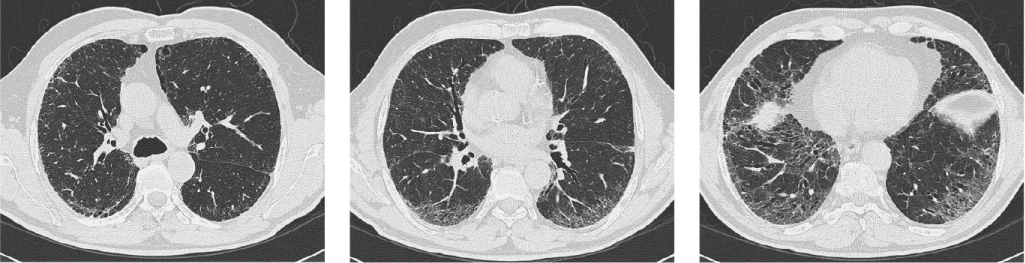

HRCT was read by two independent core radiologists according to the following protocol: three levels were selected from each HRCT (Figure 1) to evaluate six different areas (three from the right lung and three from the left lung).

Figure 1: The different HRCT levels. View Figure 1

• Upper: Everything above the level of the carina;

• Lower: Everything below the highest point of the right diaphragm;

• Middle: Between the previous two, right at the midpoint.